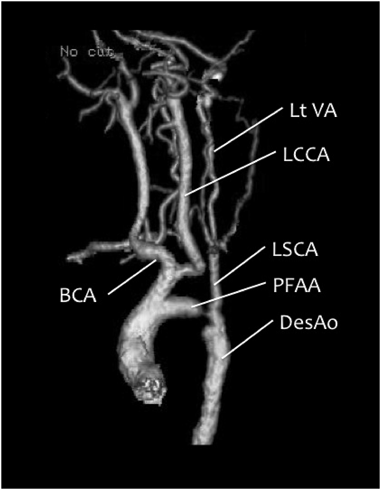

第5大動脈弓遺残に第4大動脈弓離断を合併した大動脈縮窄の2手術例Successful Repair of Coarctation of the Aorta Using Fifth Aortic Arch in Two Neonates with the Persistent Fifth Aortic Arch and Interrupted Fourth Aortic Arch